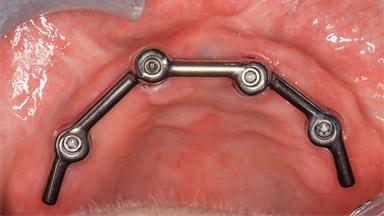

Flapless Guided Surgery: Bar-supported Overdenture on Four Implants

A female patient, born in 1934, medically compromised (Renton and coworkers 2013) (ASA III: history of CVAs, arrhythmia, high blood pressure, type 2 diabetes mellitus, hypothyroid, arthroses, and hyperventilation) presented at our clinic. Her remaining maxillary dentition had had to be extracted some years ago due to multiple periapical infections; since then, the patient had been functioning with a conventional maxillary denture. This denture had been giving her problems in terms of function, eating, and digesting food. She lived at a considerable distance from the clinic. Despite the pain while wearing and using the denture, she kept her spirits and hoped for a different solution. She wished for more comfort and better chewing ability; at the time, she could not visit friends or have dinner in a restaurant with her conventional denture.

# of Implants 4

Type of Implants One-Piece

Attachment One-Piece

Modality Overdenture on 4 implants